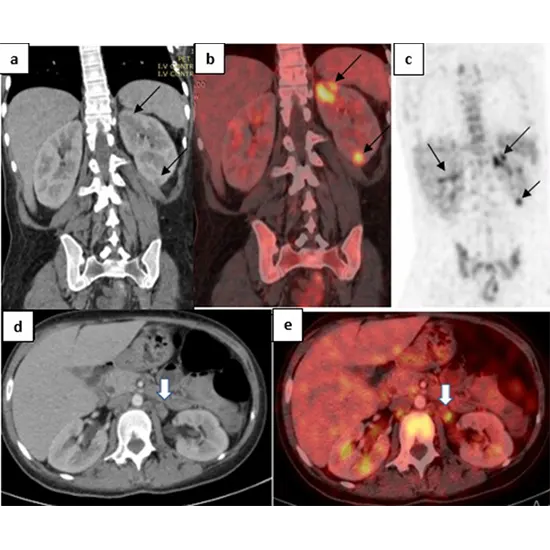

Within the setting of fever, PET CT can be utilized to assist diagnose the basic cause of the fever. PET CT can distinguish regions of inflammation or infection within the body that will not be unmistakable on other imaging strategies such as X-ray or MRI. It can also offer assistance distinguish ranges of cancer which will be causing the fever.

CT employments X-rays to form point by point pictures of the body's inside structures. When PET and CT are combined, it permits specialists to see both metabolic movement and anatomical points of interest at the same time, which can offer assistance in diagnosing the fundamental cause of a fever.

PET-CT can be valuable in cases where a fever is caused by an contamination or aggravation, because it can offer assistance to identify areas of expanded metabolic action which will be demonstrative of the nearness of disease or irritation within the body.